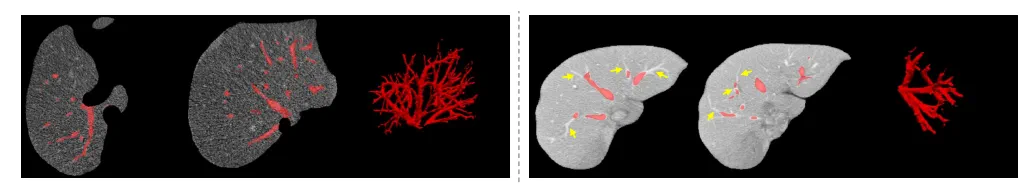

labeling liver vessel

Illustration of liver vessels. Left: what you want to label; right: what you start with from a model prediction. Figure from a paper for a different context

• Laborious Delineation: This is the meticulous, often tedious work of finding minuscule lesions or outlining structures. Think of scrolling slice-by-slice through a CT scan to find every “blob-like” lung nodule or painstakingly segmenting the intricate network of liver vessels. This work demands immense patience, focus, and dexterity.